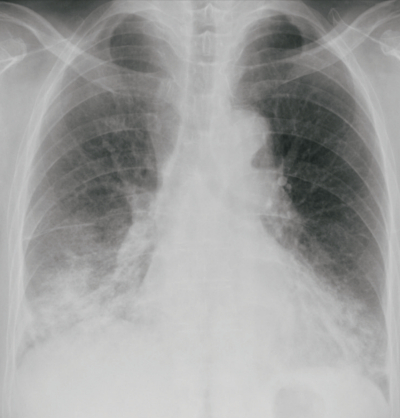

血液所見: Hb 12.2 g/dL、白血球 9,400、血小板 24万。血液生化学所見: AST 20 U/L、ALT 8 U/L、LD 293 U/L (基準 120~245)、尿素窒素 12 mg/dL、クレアチニン 0.7 mg/dL。KL-6 2.919 U/mL (基準 500未満) 。免疫血清学所見:CRP 3.6 mg/dL、β-D-グルカン 5.0 pg/mL (基準 10以下) 。抗核抗体 40倍 (基準 20以下)、MPO-ANCA陰性、PR3-ANCA陰性、抗アミノシルtRNA合成酵素抗体〈抗ARS抗体〉陽性。胸部エックス線写真及び肺野条件の胸部単純CTを示す。

呼吸状態の悪化を認め、治療を行い改善した。改善後の胸部エックス線写真を別に示す。効果を示した治療はどれか。